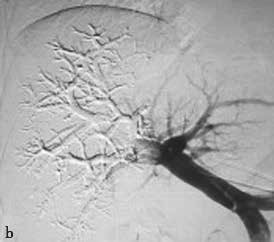

PVE栓塞材料多样,包括弹簧微钢圈、明胶微球、吸收性明胶海绵、凝血酶、超乳化碘油、纤维蛋白胶、无水乙醇、聚乙烯醇颗粒、氰基丙烯酸正丁酯(N-Butyl cyanoacrylate,NBCA)等,多种材料个体化联合应用能够增强栓塞效果(图2-5-1)。

图2-5-1 采用不同栓塞材料实施PVE

A、a.弹簧微钢圈栓塞门静脉右支;

B、b.氰基丙烯酸正丁酯栓塞门静脉右支和Ⅳ段支;

C、c.微钢圈联合氰基丙烯酸正丁酯栓塞门静脉右支。